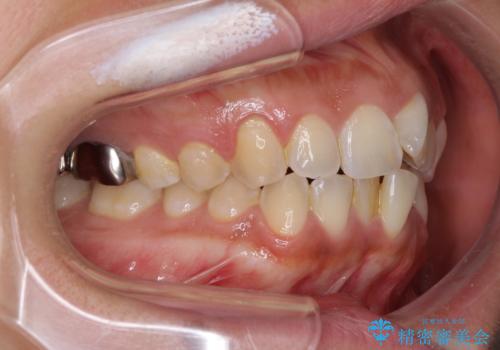

インビザラインによる狭窄歯列の拡大矯正

- 前歯のデコボコを治したいとのことで来院された患者様です。

上下顎ともに歯列全体の後方移動と側方拡大、IPR(歯と歯の間を削る)によってデコボコが解消するように設計し、インビザラインにより治療を行うこととしました。

後方移動に際し、上下の親知らずは4本とも抜歯することとしました。

治療途中で関西に転勤となってしまったため、東京に出張で来るタイミングに合わせて治療を進めることになりました。そのため、治療期間が長くなってしまいましたが、無事に仕上げることができました。